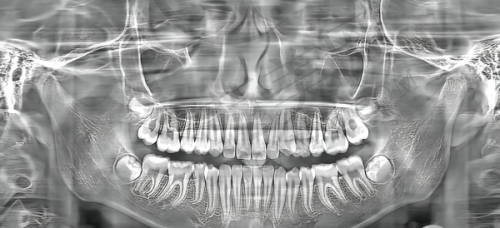

诊疗设备精良:配备数字化高端进口诊疗设备,提高手术精度,减少术后修养时间。通过数字化微创技术,医生能更好评估患者口腔状况,制定个性化治疗方案,让手术过程更舒适。

成都团圆口腔引进大视野数码全景、数字化3DexamCBCT、德国卡瓦种植机、数字化无感印模等高端口腔诊疗设备。应用欧美种植系统、正畸系统、,让种牙过程更精细化、智能化,还可提前预知种植成效,颠覆传统种植体验,满足顾客不同需求,有效提高诊疗质量,为种植牙手术提供有力支持,让患者享受更精良、更精细治疗。